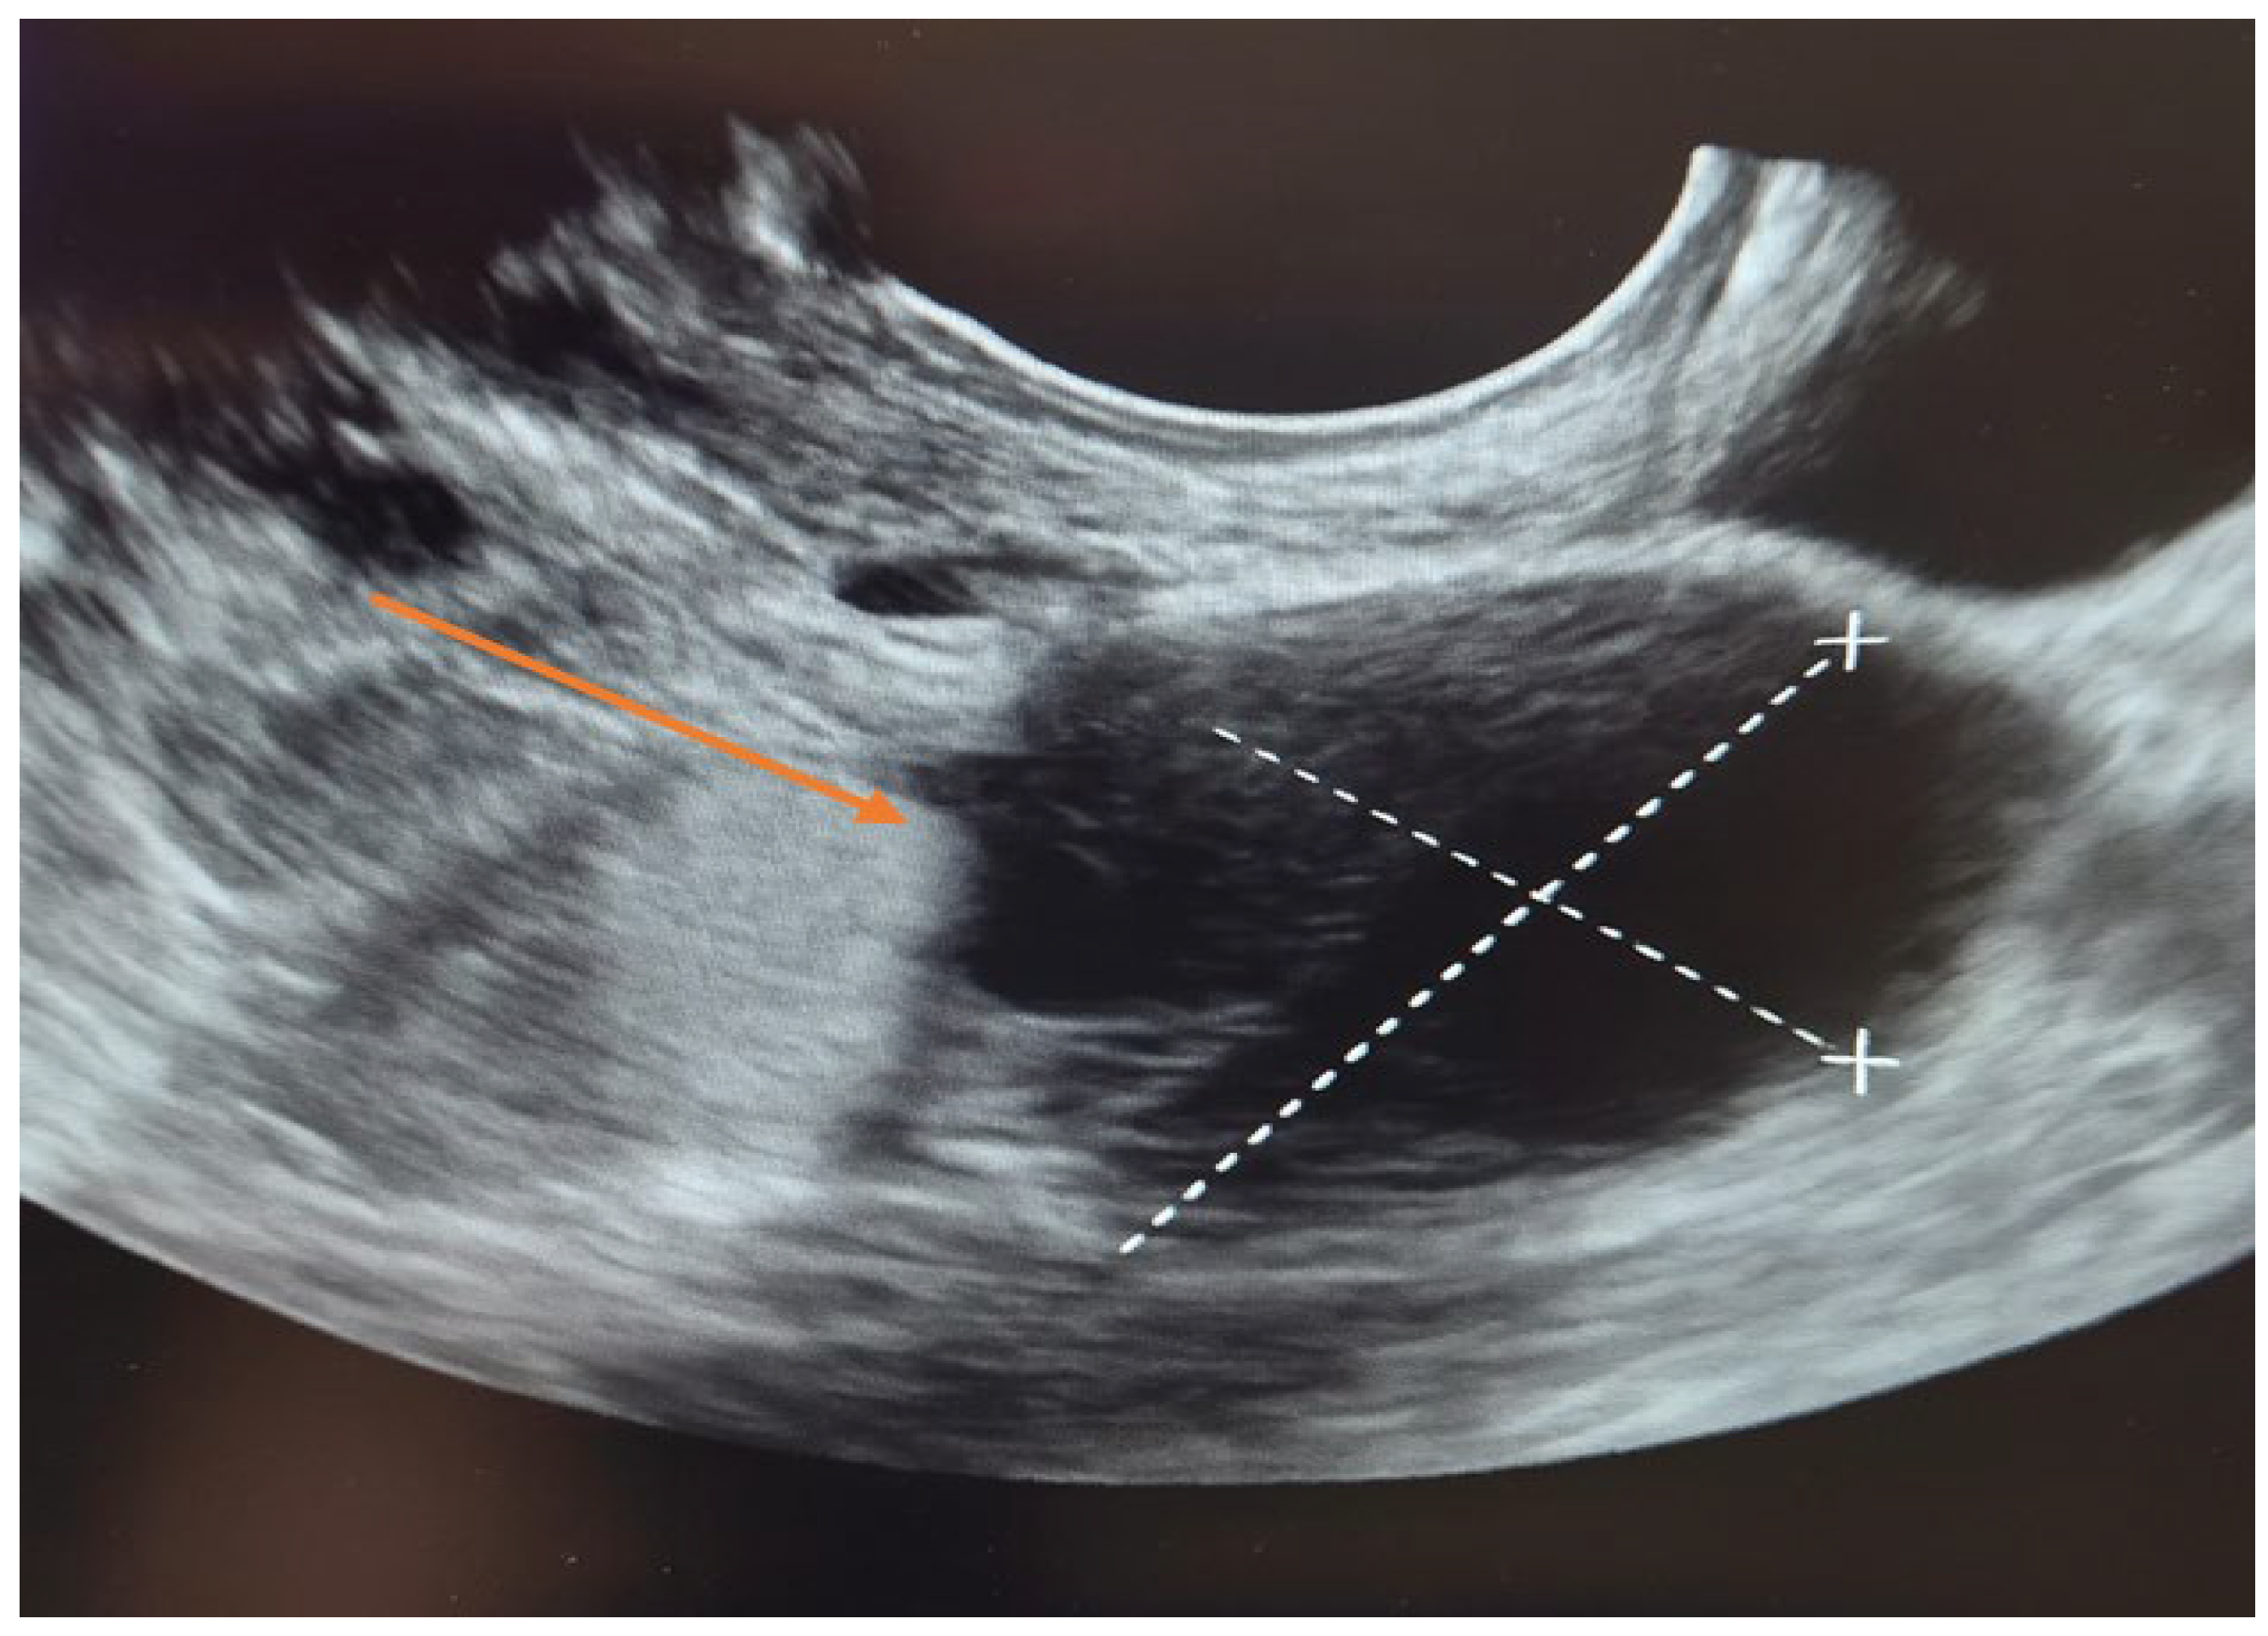

3.4. Diagnostic Assessment

The patient was first evaluated using gynecologic ultrasound, including transvaginal sonography (TVS), which is the first-line diagnostic tool for adnexal masses in clinical practice. Transvaginal sonography (TVS) revealed a complex left adnexal mass with cystic morphology, showing well-defined borders and thin internal septations (Figure 1). Subsequently, magnetic resonance imaging (MRI) was performed as a complementary investigation to provide additional characterization of the lesion and to assist in the differential diagnosis with borderline or malignant ovarian tumors.

Figure 1. Transvaginal sonography (TVS) of the left adnexa ( orange arrow) demonstrating a complex ovarian cyst with cystic morphology, thin internal septations, and well-defined borders.